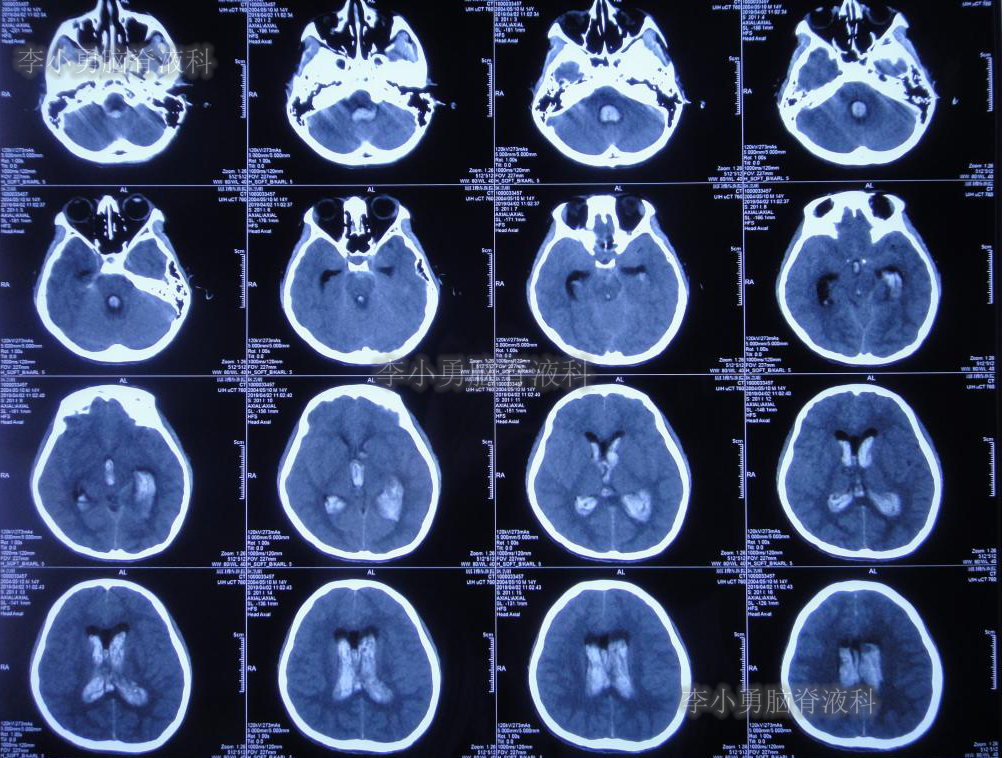

2019年3月26日患者突发头痛及呕吐,随后出现晕厥。急救车送至河南省周口市某医院。行头颅CT(图-1):脑室内出血,次日急诊给予行双侧脑室外引流术(图-2)(第一次的脑室外引流术)。

图-1:2019年3月26日头颅CT:脑室内出血

图-2:2019年3月27日头颅CT:双侧脑室外引流术后

双侧脑室外引流5天后即2019年3月31日,脑脊液颜色由血性明显变淡,意识转清,肢体活动良好,给予复查头颅CT(图-3):脑室不大,残留少许积血。

图-3:2019年3月31日头颅CT:残留少许积血

次日即2019年4月2日给予行腰椎穿刺术,引流出血性脑脊液;但腰椎穿刺术刚结束突然晕厥,再次复查头颅CT(图-4):脑室内出血量较前明显增多,四脑室及中央导水管铸形。

图-4:2019年4月2日头颅CT:脑室内积血明显增多